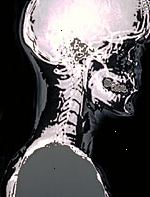

Ακτίνες Χ χρησιμοποιούν αόρατη ηλεκτρομαγνητική ενέργεια δοκάρια για να παράγει εικόνες των εσωτερικών ιστούς, τα οστά και τα όργανα σε φιλμ. Οι τυποποιημένες ακτίνες Χ εκτελούνται για πολλούς λόγους, συμπεριλαμβανομένης διάγνωση όγκους ή τραύματα των οστών.

Οι ακτίνες Χ γίνονται με τη χρήση εξωτερικών ακτινοβολία για να παράγει εικόνες του σώματος, τα όργανά του, και άλλες εσωτερικές δομές για διαγνωστικούς σκοπούς. Ακτίνες Χ διέρχεται διαμέσου των ιστών του σώματος σε πλάκες ειδικά επεξεργασμένο (παρόμοια με τα φωτογραφικά φιλμ) και «αρνητική» εικόνα τύπου γίνεται (η πιο σταθερή είναι μια δομή, τα λευκά εμφανίζεται στην ταινία).

Όταν το σώμα υποβάλλεται σε ακτίνες Χ, διαφορετικά μέρη του σώματος επιτρέπουν ποικίλες ποσότητες των δοκών ακτίνων Χ για να περάσει μέσα. Οι εικόνες που παράγονται σε βαθμούς του φωτός και του σκότους, ανάλογα με την ποσότητα των ακτίνων Χ που διαπερνούν τους ιστούς. Οι μαλακοί ιστοί του σώματος (όπως αίμα, το δέρμα, το λίπος, και των μυών) επιτρέπουν το μεγαλύτερο μέρος της Χ-Χ για να περάσει μέσα και εμφανίζονται σκούρα γκρι για την ταινία. Ένα οστών ή ένας όγκος, που είναι πυκνότερο από μαλακούς ιστούς, επιτρέπει μερικές από τις ακτίνες Χ για να περάσει μέσα και εμφανίζεται λευκό για την ακτινογραφία. Σε ένα διάλειμμα σε ένα οστό, η δέσμη ακτίνων Χ περνά μέσα από το σπασμένο περιοχή και εμφανίζεται ως μια σκοτεινή γραμμή στο λευκό οστό.

Ενώ οι ακτίνες Χ του κρανίου δεν χρησιμοποιούνται τόσο συχνά όσο στο παρελθόν, λόγω της χρήσης των νεότερων τεχνολογιών όπως η αξονική τομογραφία (CT σαρώσεις) και η μαγνητική τομογραφία (MRI), παραμένουν πολύτιμες για την αξιολόγηση των οστών του κρανίου για κατάγματα και την ανίχνευση άλλων νόσων του κρανίου και του εγκεφάλου.